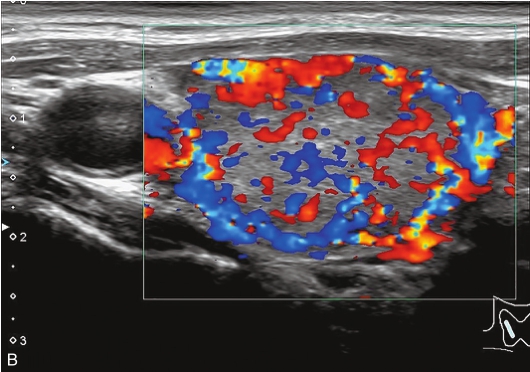

男性,52岁,外院发现甲状腺结节,为求进一步诊治收入我院。

甲状腺左叶中下部见一混合回声结节,边界清,形态规则,中心部可见斑状强回声,CDFI显示周边可见环状血流信号,其内可见丰富血流信号,见图1-3-18。

该结节早于周围腺体组织增强,结节内部呈高增强表现,可见部分无增强区;结节晚于周围腺体组织消退,仍呈高增强表现;结节周边可见均匀高增强环,甲状腺被膜未见明显中断,见图1-3-19、ER1-3-9。

(1)结节增强早期早于腺体增强或与腺体同步增强,增强晚期晚于腺体消退或与腺体同步消退。

(2)结节内部呈均匀或不均匀弥漫性等增强或高增强,增强水平通常高于周围腺体。

(3)结节与周围腺体分界清晰,形态较规则。

(4)部分结节周边可见均匀高增强环。

(5)结节周边被膜连续完整。

甲状腺滤泡性腺瘤通常为富血供病灶,其增强水平等于或高于周围腺体,并呈现“早增强,晚消退”的特点,重点需要与滤泡性腺癌鉴别,腺瘤多边界清晰、形态较规则,造影时结节周围的高增强环厚薄一致、较为均匀,结节周边被膜连续完整、无浸润表现,颈部淋巴结无异常肿大等。而滤泡性腺癌边界不清、呈浸润性生长表现,周边高增强环消失或厚薄不均,如发现颈部异常肿大淋巴结及被膜连续性中断等,需要高度警惕甲状腺恶性肿瘤。

图1-3-18 甲状腺滤泡性腺瘤常规超声声像图

A.甲状腺左叶纵切面超声图像;B.结节内部点状及斑状强回声;C.CDFI血流图

图1-3-19 甲状腺滤泡性腺瘤超声造影图

A.注入造影剂后9s;B.注入造影剂后11s;C.注入造影剂后16s;D.注入造影剂后27s